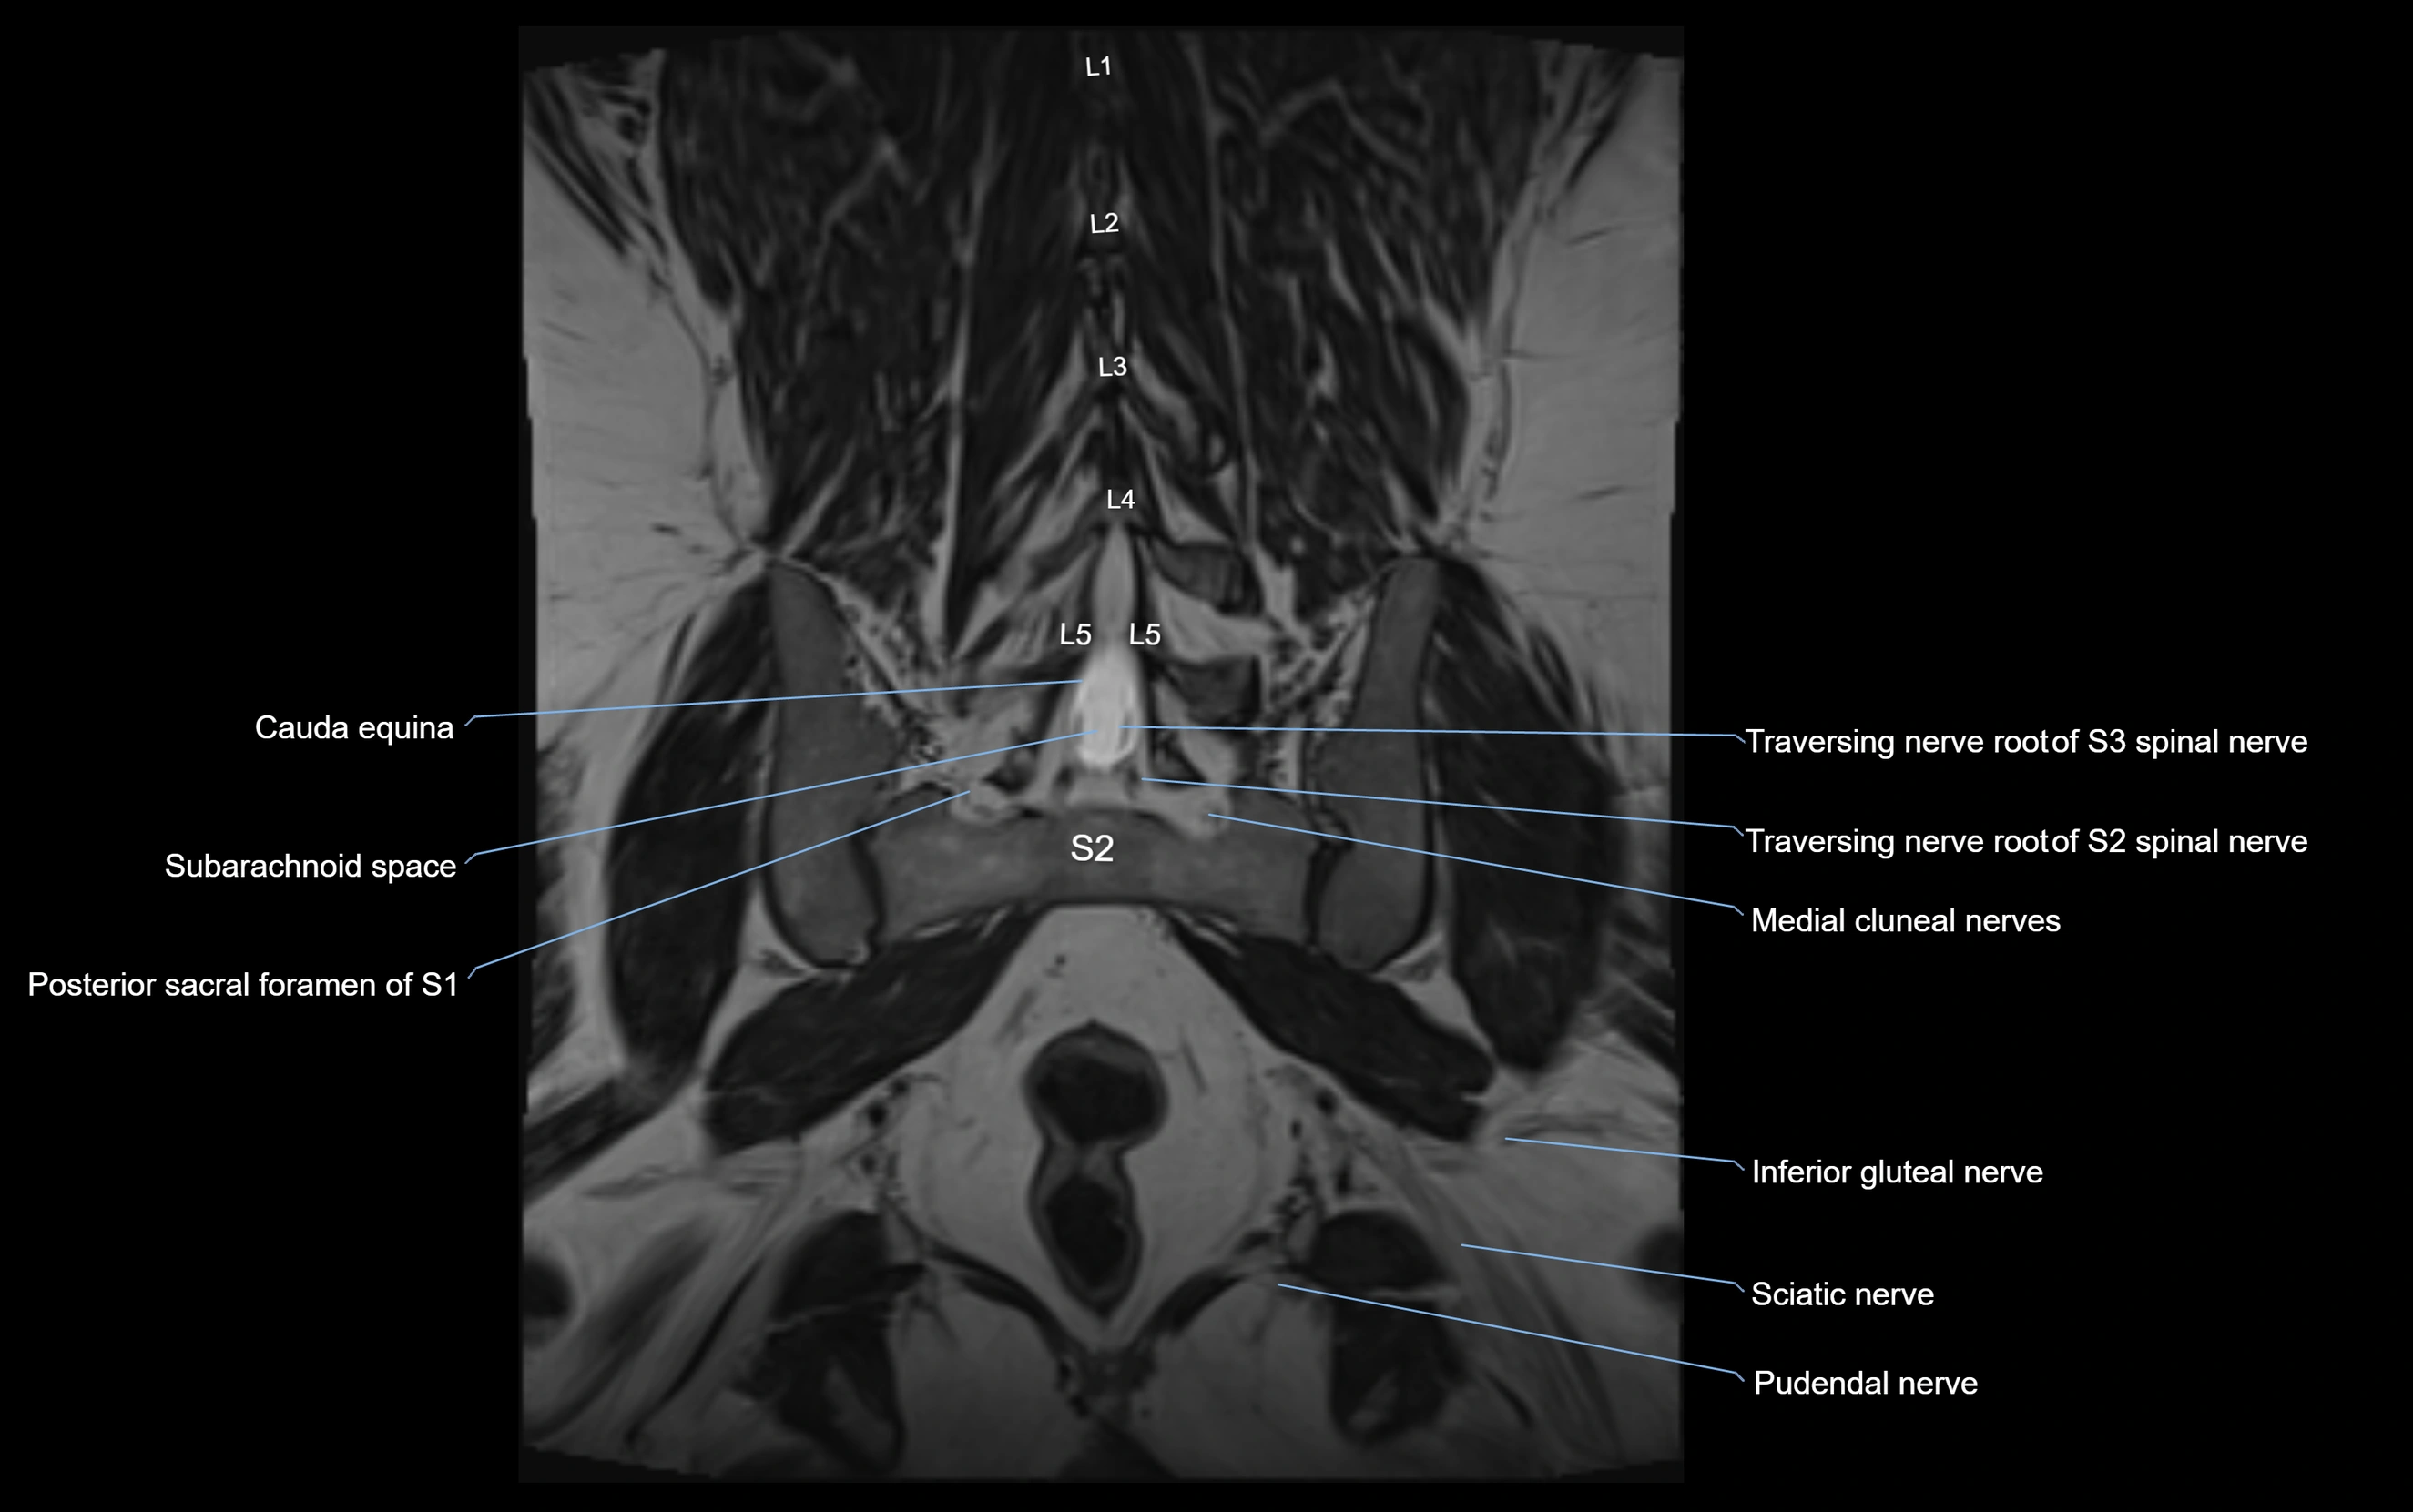

MRI image

image